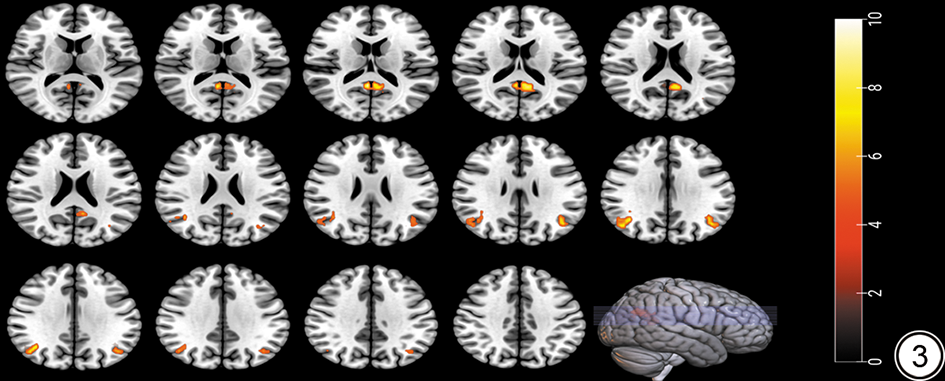

其中三组间基于左侧内侧额上回为种子点的FC值差异有统计学意义的脑区:右侧楔前叶及双侧角回。事后分析结果显示:与NGT组对比,T2DM组右侧楔前叶的FC值增加,PreDM组双侧角回的FC值减低;与PreDM组对比,T2DM组右侧楔前叶及双侧角回的FC值增加。结果详见表4图3

图3  T2DM组、PreDM组和NGT组左侧内侧额上回为种子点FC值差异有统计学意义的脑区。右侧色带条颜色越亮代表统计值F值越大。T2DM:2型糖尿病;PreDM:糖尿病前期;NGT:糖耐量正常;FC:功能连接。

Figure 3  Brain regions with statistically significant FC values differences in the T2DM, PreDM and NGT groups using the left medial superior frontal gyrus as the seed point. The brighter the color of the ribbon on the right, the greater the F value. T2DM: type 2 diabetes mellitus; PreDM: prediabetes mellitus; NGT: normal glucose tolerance; FC: functional connectivity.